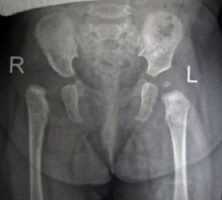

Рентгенограммы больной Т., 10 месяцев. Диагноз: врожденный вывих бедра справа.